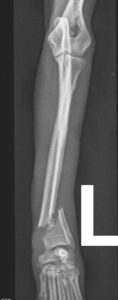

Der Unfall war typisch für Zwerghunde. Aufgeregt war Hugo (Name geändert) so lange zwischen den Beinen seines Halters herumgewuselt, bis dieser ihm aus Versehen aufs Beinchen trat. Die Folge: Der gerade mal 2,3 Kilo schwere Prager Rattler landete mit einem offenen Unterarmbruch auf dem OP-Tisch von Dr. Klaus Zahn. Mit einer feinen, dem zarten Körperbau angemessenen Platte versorgte dieser die Fraktur, und Hugo wurde nach Hause entlassen.